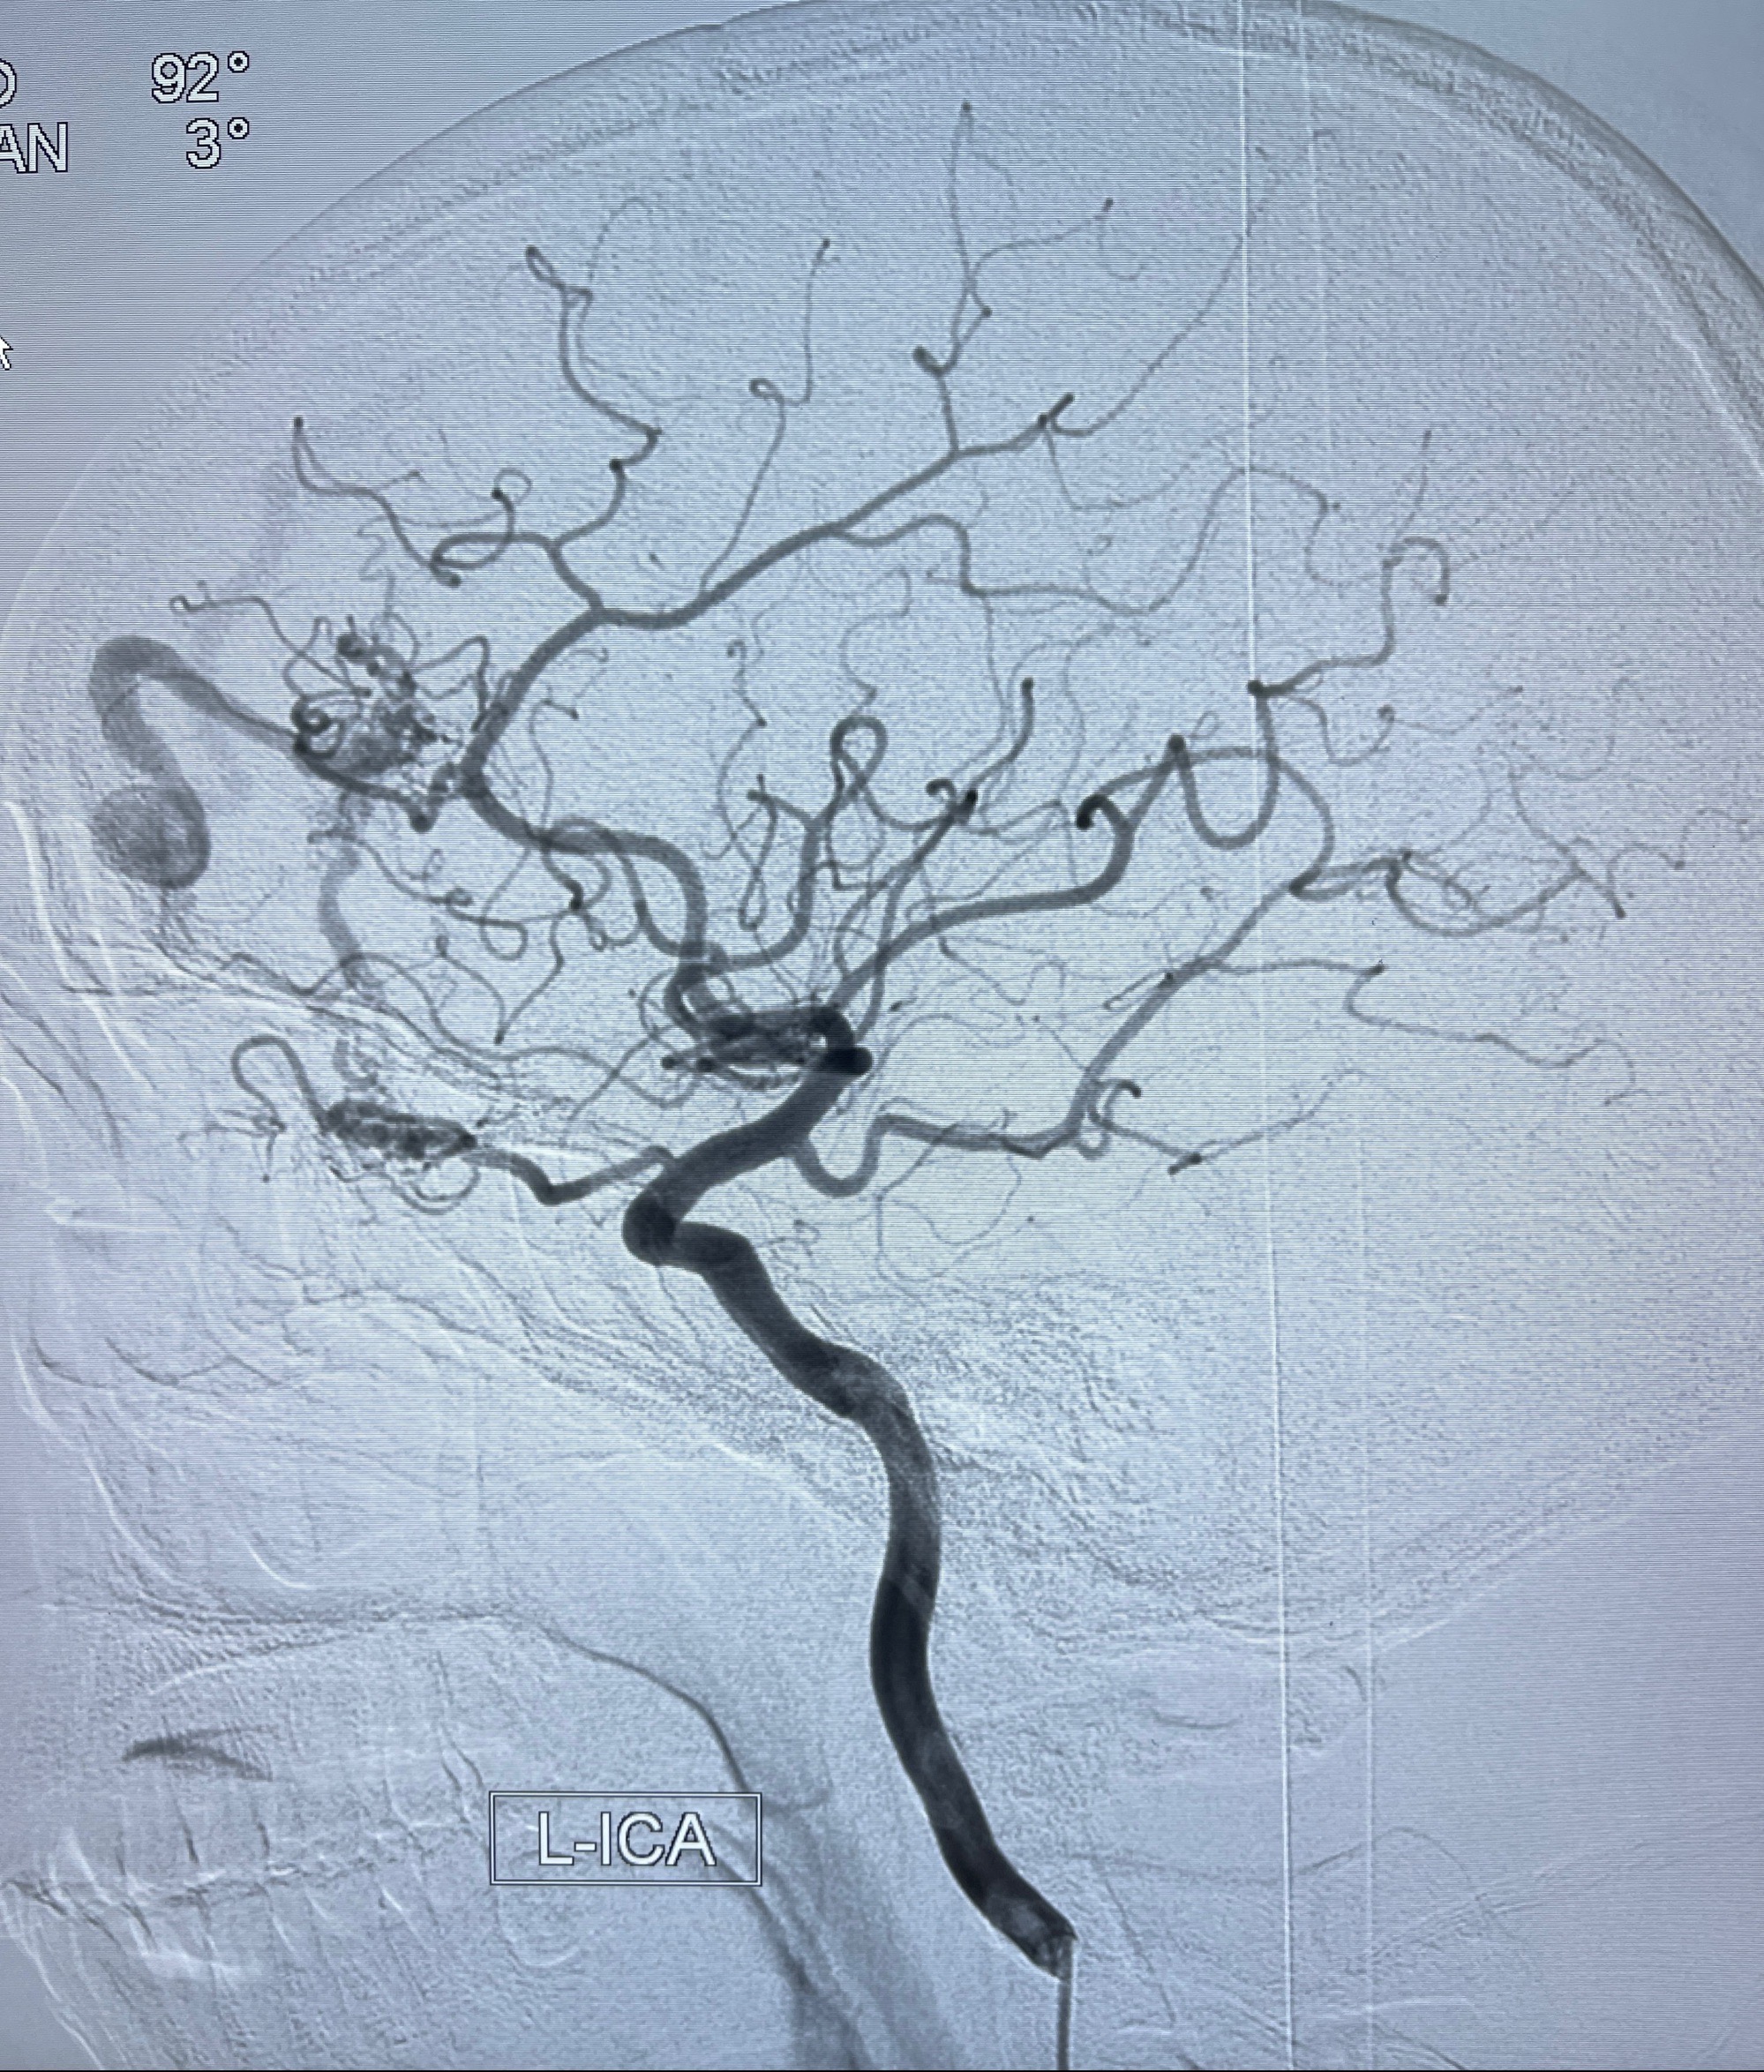

2023年8月21日]景德镇市第一人民医院脑血管造影检查,提示:主动脉弓、双侧颈总动脉、锁骨下动脉造影未见异常,左侧大脑前动脉静脉瘘。

2023-09-13全脑血管造影:前颅底硬脑膜动静脉瘘,供血动脉为双侧胼周动脉、眼动脉脑膜支,静脉向上矢状窦方向引流